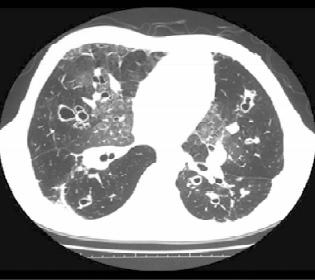

支气管扩张典型表现见图2-2和图2-3。

图2-3 双下肺成簇囊状扩张,伴局部肺大疱